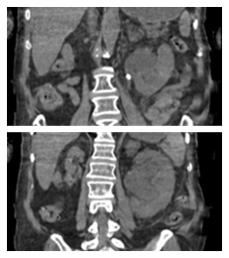

Introducing STONE PASS A community education effort to improve ureteral stone discussions between patient & provider A tool to communicate probability based on outcomes of similar patients (size, location, & #PROMIS pain) It's all about decision making stonepassapp.com